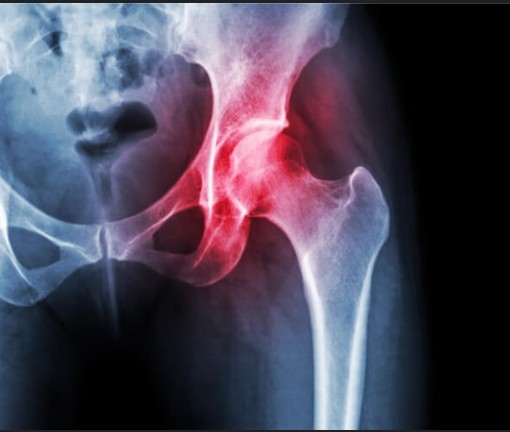

استبدال مفصل الحوض ا ع م

مُسن في السبعين  من عمره  يسكن مع أسرته ذات الدخل المحدود  وغير قادر على تغطية تكاليف علاجه ، يعاني من خشونة شديدة  وخلع بمفصل الحوض الايسر  و  يحتاج  لإجراء عملية استبدال مفصل حوض صناعي كامل  تبلغ التكلفة  32,545 ريال  وتضاف إليها النسبة التشغيليه 10% تصبح التكلفة الاجمالية 35,710  ريال, وهو ينتظر عطاءكم الكريم لتخفيف معاناته  ويكون سببًا في شفائه بإذن الله.